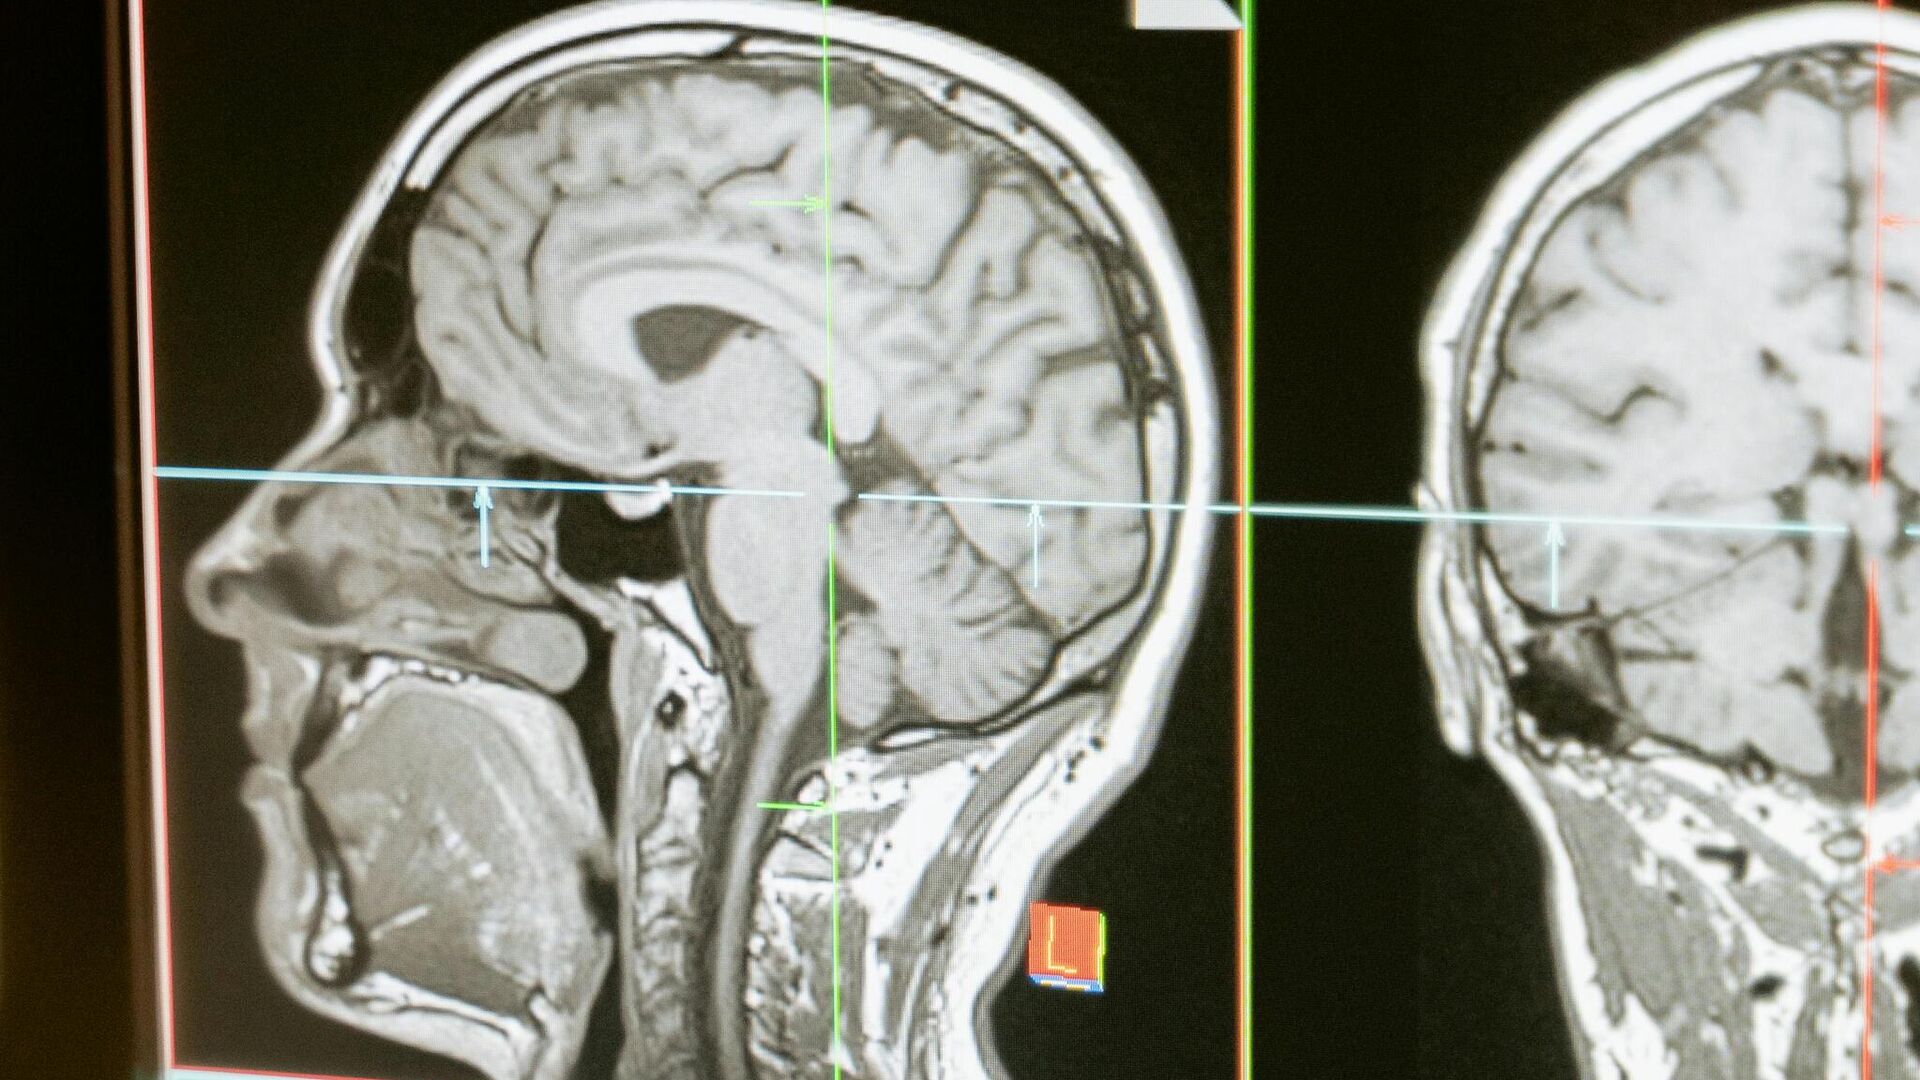

Ono što je posebno interesantno u vezi s novom studijom jeste da su se promene u moždanoj aktivnosti zabeležene funkcionalnom magnetnom rezonancom (FMRI) dogodile upravo u regionima za koje se zna da su važni u regulaciji apetita i zavisnosti – uključujući inferiorni orbitalni frontalni režanj.